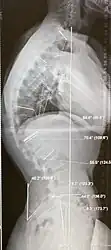

Scheuermann's disease, showing various measurement of kyphotic/lordotic degrees and their supplementary angles. Notice the signature 'wedging' shape of the four vertebrae in the lower thoracic area. The other vertebral bodies are otherwise normal.

Diagnosis is typically by medical imaging. The degree of kyphosis can be measured by Cobb's angle and sagittal balance.